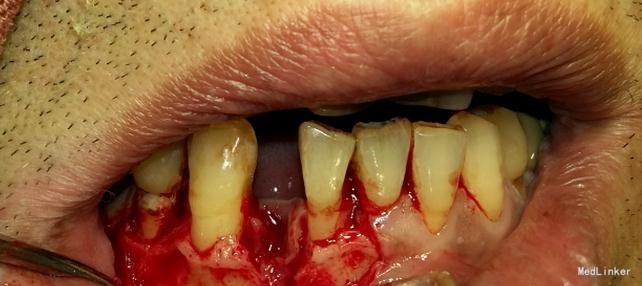

患者,男,45岁,右侧下颌侧切牙严重龋坏,拔除后要求种植修复,平素体质一般,无药物、食物过敏史,无高血压、心脏病等系统病史

种植修复

效果很好,患者满意